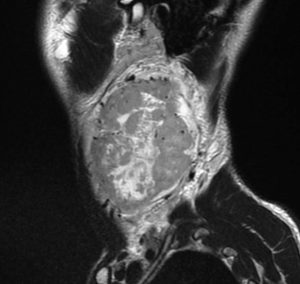

遺伝歴があり30代くらいです。黄色の矢印で示す右側はglomus vagale,左側は上がglomus jugulare、左下がglomus caroticumです。教科書に載せたいくらい典型的な部位に発生しています。無症状ですからもちろん治療はしません。6年くらい経過観察していますがほとんど増大もしません。